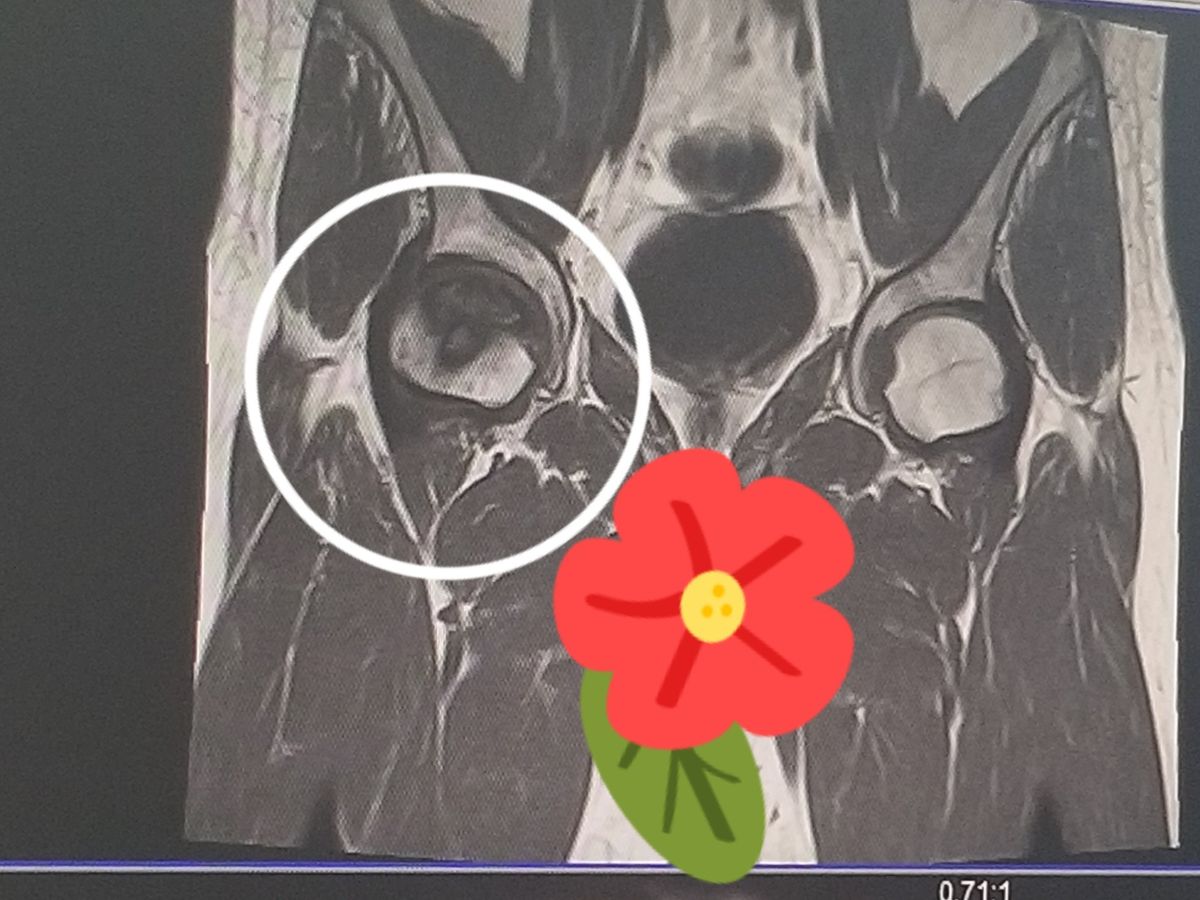

So, after getting advice and encouragement from my wonderful girlfriend, friends and family, I finally went into the doctor to figure out what was going on. X Ray's and an MRI have revealed that I have stage 4 osteonecrosis in my hip and a torn meniscus in my knee. Given that several hundred people in D.C. die in bicycle accidents yearly, I have to count myself lucky that was all the damage done. However, I am in no way shape or form able to afford the required hip replacement surgery. The surgery is the only viable method of treatment and there is no cure. Time is also a large factor as it is possible that my hip bone could collapse into itself.